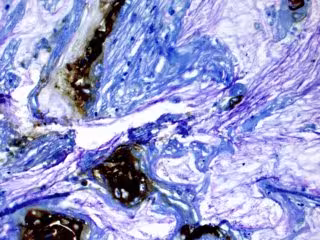

Archivo - Las áreas marrones se tiñen para un biomarcador en el tejido de un paciente que desarrolló cáncer de páncreas a partir de un quiste.

Archivo - Las áreas marrones se tiñen para un biomarcador en el tejido de un paciente que desarrolló cáncer de páncreas a partir de un quiste. - KOUSHIK DAS, MD - Archivo